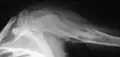

X-ray showing enchondromas localized in the lower part of the radius of a 37-year-old patient affected with Ollier disease